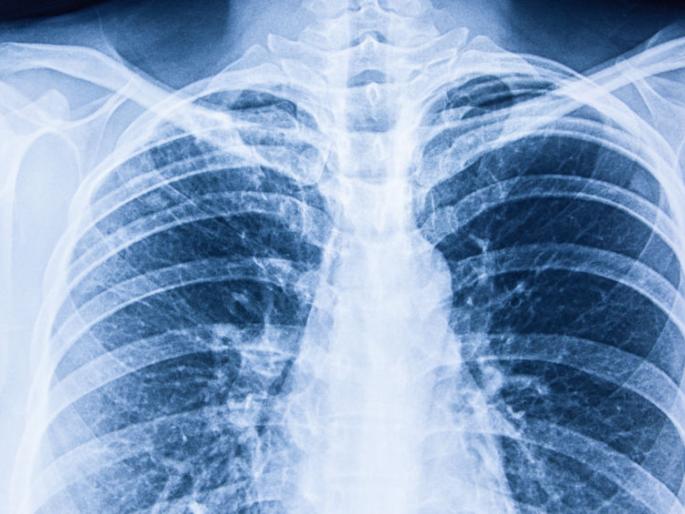

एक्स-रेमध्ये संशयित रुग्णाच्या फुप्फुसांमधील संसर्गाचे प्रमाण दिसून येते. हा प्रयोग यशस्वी ठरल्यानंतर अन्य जम्बो फॅसिलिटी सेंटरमध्ये रुग्णांचे एक्स-रे काढून बाधित रुग्णांवर उपचार सुरू करण्यात आले.

मुंबई : कोरोना रुग्णांचा अहवाल झटपट मिळण्यासाठी महापालिकेने गेल्या महिन्यापासून अँटिजन चाचणी सुरू केली. त्याचबरोबर आता थेट संशयित रुग्णाच्या छातीचा एक्स-रे काढून संसर्गाचे निदान तत्काळ करण्यात येणार आहे.

आतापर्यंत कोविड केअर सेंटरमधील संशयित आणि लक्षणे नसलेल्या रुग्णांचे एक्स-रे काढण्यात येत होते. मुंबईत अशा सात एक्स-रे व्हॅन बाधित क्षेत्रांमध्ये रुग्णांचा शोध घेणार आहेत. मुंबईत आतापर्यंत आरटीपीसीआर चाचणी करण्यात येत होती. मात्र या चाचणीचा अहवाल येण्यासाठी किमान २४ तासांचा कालावधी लागतो. त्यामुळे अर्ध्या तासात अहवाल देणाऱ्या अँटिजन चाचणीचा वापर महापालिकेने गेल्या महिन्यात सुरू केला. त्याचबरोबर वरळी येथील नॅशनल स्पोटर््स क्लब आॅफ इंडियाच्या विलगीकरण कक्षात एक्स-रे मशीनचा वापर सुरू करण्यात आला.

एक्स-रेमध्ये संशयित रुग्णाच्या फुप्फुसांमधील संसर्गाचे प्रमाण दिसून येते. हा प्रयोग यशस्वी ठरल्यानंतर अन्य जम्बो फॅसिलिटी सेंटरमध्ये रुग्णांचे एक्स-रे काढून बाधित रुग्णांवर उपचार सुरू करण्यात आले. लक्षणे नसलेल्या रुग्णांचेच नव्हे तर चाचणी अहवाल निगेटिव्ह आलेल्या रुग्णांचे एक्स-रे काढून त्यांच्यामध्ये विषाणू असल्यास दिसून येत आहे. त्यामुळे चाचणीबरोबरच हा प्रयोगही रुग्णांना शोधण्यास प्रभावी ठरत आहे. संशयित रुग्णाचा एक्स-रे काढल्यानंतर पालिकेच्या तज्ज्ञ डॉक्टरांमार्फत त्याची तपासणी केली जाणार आहे. त्याच्यावर तत्काळ उपचार सुरू करण्यात येतील.

काही बाधित क्षेत्रांमध्ये नियमित फिव्हर कॅम्प आयोजित करण्यात येत आहेत. तेथे येणाºया संशयित रुग्णांचे एक्स-रे प्राधान्याने काढण्यात येतील़

मुंबईतील सात परिमंडळात एक्स रे व्हॅन सुरू करण्यात आल्या आहेत. या व्हॅनचा वापर कुठे आणि कसा करावा? याचे नियोजन संबंधित विभागाच्या सहाय्यक आयुक्तांमार्फत करण्यात येईल. त्या रुग्णांचे एक्स रे रेडिओलॉजिस्टकडे पाठवण्यात येणार आहेत. यामध्ये संसर्ग दिसून आलेल्या रुग्णावर उपचार सुरू करण्यात येणार आहे.